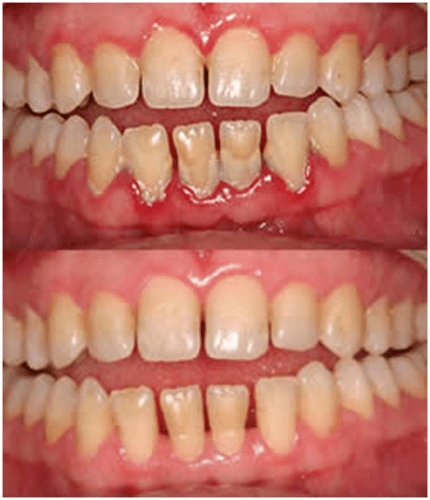

At Astha Multi Speciality Dental Clinic, Palanpur, we offer Gingival Flap Surgery, a proven and effective procedure to treat moderate to advanced gum disease (periodontitis/pyorrhea). In this procedure, the gums are gently lifted away from the teeth to provide deep access to the roots and underlying bone, allowing thorough cleaning and treatment of infected tissues.

This advanced periodontal procedure helps restore gum health, eliminate infection, and support the long-term stability of your teeth.

If your gums are receding, swollen, or bleeding frequently, you may be a candidate for flap surgery to restore healthy attachment between the gums and teeth.